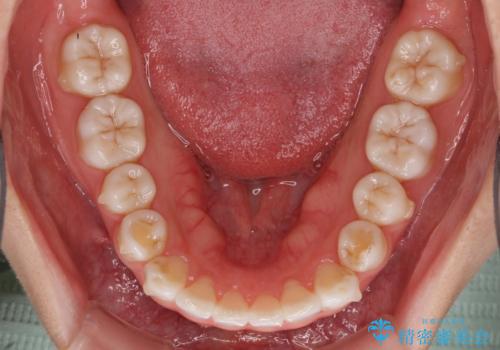

- 上の前歯の出っ歯を治したいとのことで来院された患者様です。

上下顎ともにIPR(歯と歯の間を削る)と歯列全体の拡大によって口元が引っ込むように設計し、インビザラインにより治療を行うこととしました。